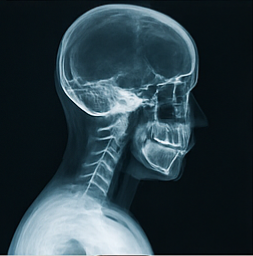

진단 절차·검사 지표

- 청력 검사: 250Hz·500Hz에서 25dB 이상 저하가 반복되면 의심된다. 내 경우 40dB까지 떨어졌다가 관리 후 20dB로 회복했다.

- 전기안진도: 눈 떨림 패턴으로 전정 기능 이상을 확인한다. 회전성 안진 지속 시간이 길수록 중증이다.

- 내림프 수종 영상: 3T MRI 가돌리늄 강화 촬영으로 내림프 팽창 유무를 시각화한다.